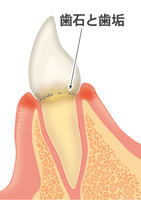

最初歯垢は柔らかいものですが、ツルツルした歯と歯肉の状態でも磨かずに放っておくと、

唾液をはじめとする様々な成分で石灰化してきます。それが歯石です。

歯石は石灰化した塊で、岩のようなものですので、岩自体が悪さをすることはありません。

ただし歯石がたまると歯の表面が形態的にラフになり、そこに歯垢がたまりやすくなります。